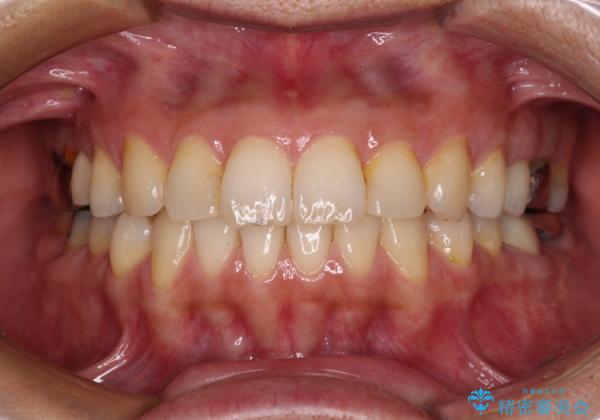

痛む奥歯と矯正の後戻り インビザライン・ライトとセラミック治療

- 高校生の時に行った矯正治療の後戻りと、通院してもなかなか改善しない奥歯の痛みを気にして来院された患者様です。

左下奥歯は、前医より難治性なので抜歯も考えるよう言われたそうですが、一度もラバーダムを用いた根管治療はされていないとのことでした。

まずは左下奥歯の根管治療を行い、痛みが引いたことを確認してから矯正治療を開始しました。

後戻りは軽微であったため、インビザライン・ライトにて歯列を整えました。

矯正治療後には、左下奥歯の症状がないことを確認し、セラミッククラウンにて補綴治療を行うこととしました。